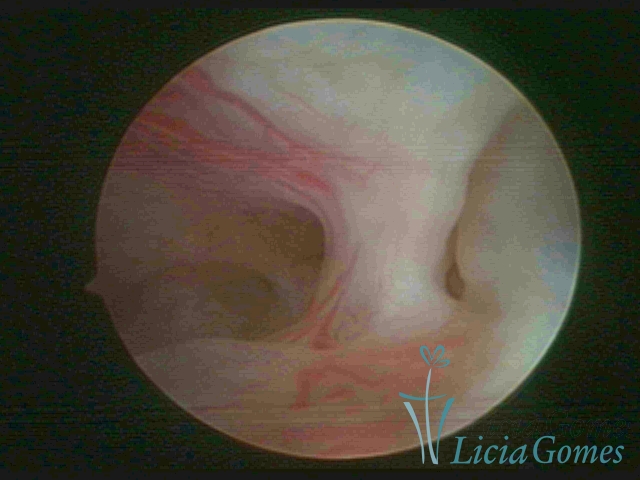

• SINÉQUIA TIPO FIBROSA